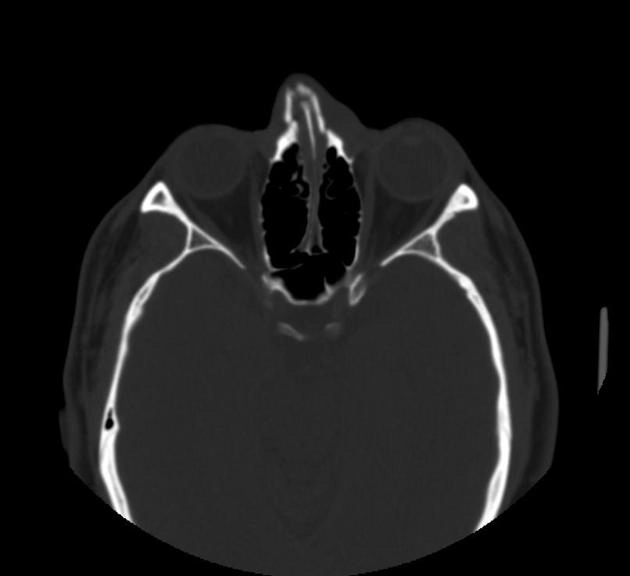

• Chấn thương hàm mặt

• Gãy xương đơn giản